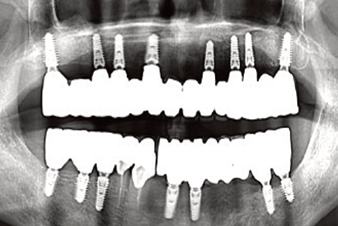

Clinical case: AFull transition from natural teeth to all-on-6 bridges

with AnyRidge implants

- Courtesy of Dr. Rabih Abi Nader, UAE -

Keywords

Full-mouth rehabilitation, minimal layering, Zirconia, all-on-6, life changing result, edentulous ,Dr. Rabih Abi Nader, AnyRidge

Products:

AnyRidge implant system